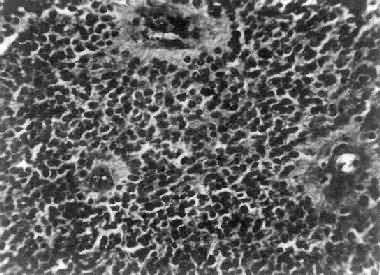

图16-24 多形性胶质母细胞瘤 发生于儿童、青少年的毛发细胞型星形胶质细胞瘤,生长极为缓慢。有报道称患者在不完全切除肿瘤后有带瘤存活达40年者。该瘤常位于小脑、第四脑室底部、第三脑室、丘脑和视神经。其形态特点是由双极性的肿瘤细胞两端发出纤细的毛发状突起。即使有毛细血管增生,本瘤的预后仍相对较好。 应该指出,同一肿瘤的不同区域,瘤细胞可有不同的形态特征,且分化程度也不尽相同,因此肿瘤的分型仅具有相对的意义。 星形胶质细胞瘤的细胞骨架含有胶质纤维酸性蛋白(GFAP),免疫组织化学染色呈阳性反应,是该肿瘤的特异标志。 2.少突胶质细胞瘤(oligodendroglioma) 约占颅内胶质瘤的5%,主要见于30~40岁的成人,男女发病的机会相等。本瘤绝大部分位于大脑半球皮质的浅层,尤以左额叶为多见。 肉眼观,肿瘤呈灰红色边界清楚的球形肿块,位于白质和邻近的皮质,并可累及软脑膜。囊性变、出血和钙化颇为常见,其中钙化灶对X线诊断有一定帮助。 镜下,瘤细胞大小均匀,形态单一,弥漫排列,胞核居中着色深,胞浆空,环绕胞核形成空晕。间质富有血管,有不同程度的内皮细胞增生。约有20%病例可出现瘤细胞钙化,其范围大小不一,其中7%为镜下钙化,有时钙化灶较大,可在X线片上显示出来。如肿瘤组织中混有星形胶质细胞瘤成分达到50%,则称混合性少突星形胶质细胞瘤。 本瘤生长缓慢,病程可长达10~30年,临床表现多为癫痫和局部性瘫痪。少数生长迅速,酷似多形性胶质母细胞瘤,预后不佳。 3.室管膜(细胞)瘤(ependymoma)起源于室管膜细胞,患者多为儿童和青少年。本瘤占颅内胶质瘤的5%~6%,多见于第四脑室,其次为侧脑室、第三脑室和导水管。脊髓病变多发生于腰胝及马尾部。 肉眼观,颅内室管膜瘤呈膨胀性生长,边界清楚,呈球形、分叶状或乳头状,肿瘤多在脑室内生长。切面灰白色,呈均匀或颗粒状,可发生灶性出血甚至坏死或囊性变,有时也可发现点状钙化。 镜下,瘤细胞大小形态一致,呈梭形或胡萝卜形,胞核圆或椭圆,染色质呈细颗粒状,核膜清楚,有核仁。瘤细胞胞浆丰富,突起明显。瘤细胞的排列有二种特征,一是环绕空腔排列成腺管状,形态上与室管膜腔相似,称为菊形团形成,另一是环绕血管形成假菊形团结构,瘤细胞有细长的胞浆突起与血管壁相连(图16-25)。细胞中有神经胶质纤维,以PTAH染色在个别细胞的腔面或胞核旁可见纤毛体,后者与纤毛运动有关,是室管膜细胞的特征性结构。此外,有时还可形成乳头状结构。发生在脊髓圆锥和终丝的肿瘤,乳头状结构轴心中的结缔组织往往富含粘液。

图16-25 室管膜瘤 瘤细胞为圆形或卵圆形,核染色质丰富,胞浆少,可见有细长的胞浆突起与血管相连,呈放射关,形成假菊形团 (二)髓母细胞瘤 髓母细胞瘤(medulloblastoma)好发于儿童,仅次于星形胶质细胞瘤而占第2位,其发生率占儿童颅内肿瘤的25%,发病年龄75%为15岁以下,偶见于成人,男性较女性为多(2~3:1)。 本瘤来源于小脑蚓部的原始神经上皮细胞或小脑皮质的胚胎性外颗粒层细胞,故本瘤主要见于小脑,在儿童多发生于小脑蚓部,在成人则多见于小脑半球。 肉眼观,瘤组织呈鱼肉状,色灰红。镜下,肿瘤由圆形、椭圆形或胡萝卜形细胞构成,胞核着色深,胞浆少而边界不清楚,有多少不等的核分裂像。细胞密集,间质中有纤细的纤维,血管不多。瘤细胞环绕一个嗜银性纤细的神经纤维中心作放射状排列形成典型的菊形团(图16-26),这对髓母细胞瘤的病理诊断有一定的意义。瘤细胞具有向神经元及神经胶质双向分化的潜能,既能向神经母细胞、节神经细胞分化,也能向胶质母细胞、星形胶质细胞分化。如瘤细胞侵入软脑膜,可在蛛网膜下腔脑脊液中广泛播散转移。